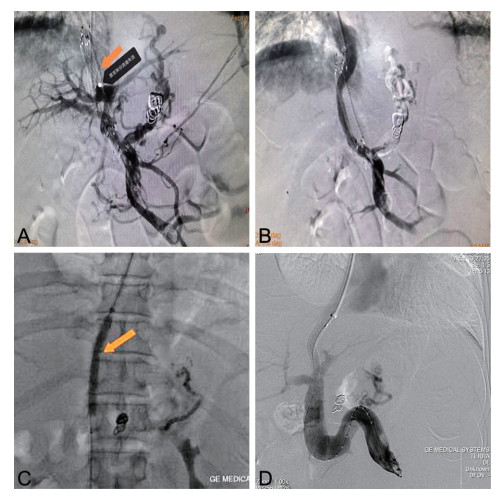

摘要:

通过回顾成人腹型过敏性紫癜误诊病例,分析原因并结合临床文献资料,总结腹型过敏性紫癜疾病特点,降低误诊率。本文回顾分析了2022年7月收治的1例被误诊为急性胃肠炎的成人腹型过敏性紫癜患者的临床资料,该例患者在腹痛后期出现皮肤紫癜,同时寻求多学科会诊,更改诊断为腹型过敏性紫癜,予以糖皮质激素、抗过敏药物等对症治疗后病情好转出院。腹型过敏性紫癜少见,而成人发病率更低,因缺乏特征性临床表现及特异性辅助检查,误诊率高,临床工作者应吸取经验教训,避免误诊错治。